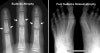

Cf) 수덱 위축(Sudeck atrophy)

골절이나 타박상 후에 생기는 벌레 먹은 모양의 골위축입니다.

RSD와 마찬가지로 통증, 종창, 피부의 위축을 동반합니다.